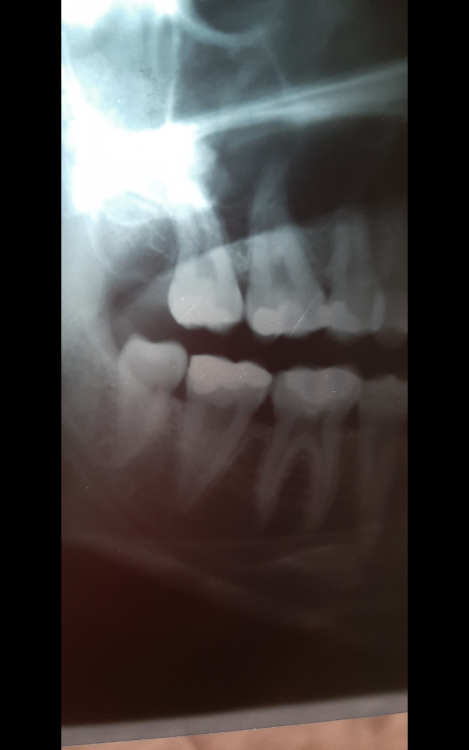

Лана-Лана Опубликовано 1 октября, 2021 Поделиться Опубликовано 1 октября, 2021 Добрый день уважаемые врачи, это опять я с продолжением темы, не знаю как лучше продолжать старую или начать новую тема( заранее извиняюсь) . Поставили мне коронку ( 7ка), при примерке я сразу обратила внимание что коронка ниже чем мои зубы, вернее бугры очень низкие и плоские , зуб практически как пенек, но ортопед сказал что у меня так и был свой видимо низкий , посмотрела на слепки и там все хорошо с этой коронкой. Я доверилась врачу, установили. Но дома я положила на зуб тонкую атласную ленту закрыла рот и она вытащилась ..ещё более менее на контакте с шестеркой а на контакте с восьмым зубом ну практически около десны..и теперь при жевании твердого немного больно десну в той области где коронка совсем низкая. Сказать что я расстроилась ничего не сказать, коронка цирконевая дорогая, что за криворукие техники... Что теперь делать? Может зуб чуть поднимется? Оцените если можно по фото...прилагаю так же снимки до депульпации зуба и после ,видно что он практически одного размера по высоте с другими зубами. И ещё момент в моем случае так неизбежна была вкладка? Почему врач всегда настаивает на вкладке? У меня что сильное разрушение зуба? Штифт ни как не хочет ставить. Цена то в два раза дороже выходит . Ссылка на комментарий

Лана-Лана Опубликовано 1 октября, 2021 Автор Поделиться Опубликовано 1 октября, 2021 (изменено) Это другой был зуб...так контакта нет с соседнем зубом и пища набивается, форма да не нравилась но я с этим смирилась и благо не в зоне улыбки!!! здесь другая проблема нет контакта с верхними зубами, и очень низкий и больно десну когда что то твердое попадает.. Как бы за 30 т за коронку ждёшь более лучшего результата и более точного исполнения ... Изменено 1 октября, 2021 пользователем Лана-Лана Ссылка на комментарий